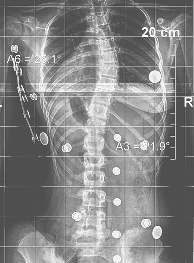

Scoliosis after 40 ° is more difficult to correct because the scoliosis and its deformities have passed to the vertebrae, creating what we call plastic deformity. This means that the treatment must be more intense and longer lasting.

Our results are very good reducing the angle to at least half of the original.

Children like this in the example, whose angle reached 120⁰ because he did not want to wear a brace at a young age.